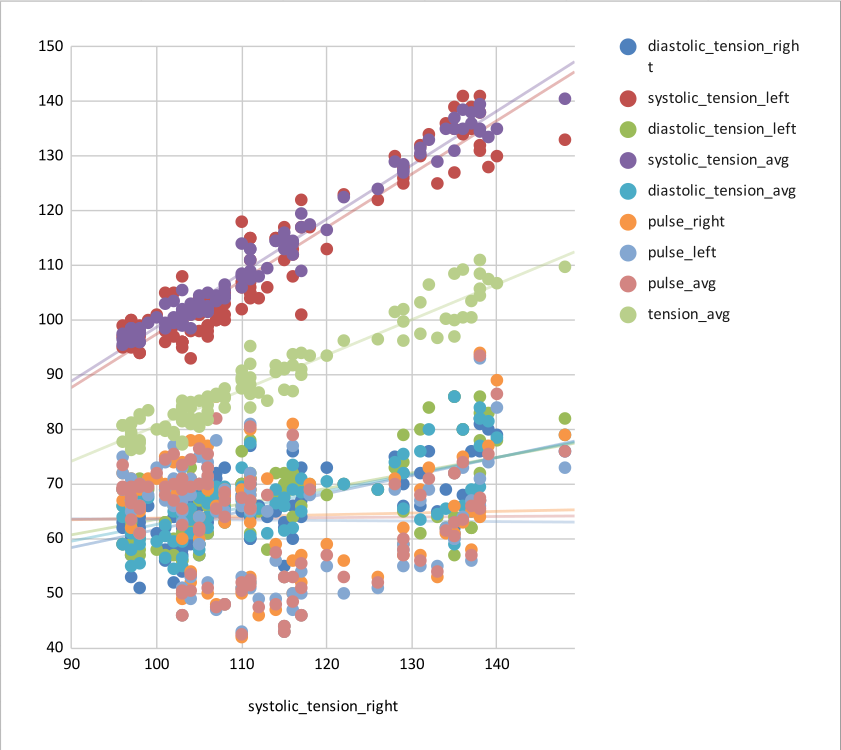

CVR and blood pressure

Due to its nature as homeostatic and cerebrovascular process, CVR is modulated by systemic changes in blood pressure¹

1. Fierstra et al. 2013 (J. Physiol.); 2. e.g. Hetzel et al. 1999 (Stroke)

Previous studies with Transcranial Doppler Ultrasound suggest to take into account blood pressure when measuring CVR²

To our knowledge, the impact of blood pressure on BOLD-fMRI based CVR estimation has not been assessed yet

Vital signs (VS), measured before the MRI session, while the subject was lying supine on a bed, once on the left arm and once on the right arm:

- Cardiac pulse

- Blood pressure (systolic and diastolic)

We averaged the two measurements and computed the Mean Arterial Pressure (MAP) and the Pulse Pressure (PP):

Correlation between VSs

Correlation between VSs

Results: blood pressure

Results: blood pressure

Results: blood pressure

Both MAP and PP should be taken into account in CVR experiments, especially in comparisons between subjects or between regions!

- Stationary blood pressure changes, expressed as MAP and PP, as well as sex, impact regional CVR estimation differently across sessions and subjects

Dynamic blood pressure changes are expected to impact CVR estimation, hence continuous blood pressure recordings are required to assess the matter